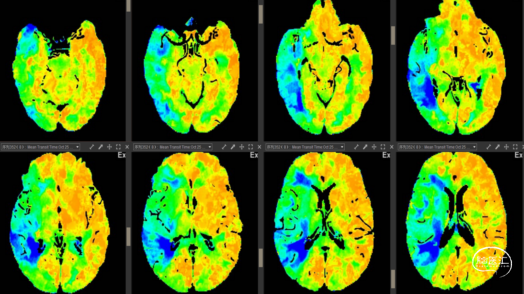

2023-10-25 术前MTT右侧大脑中动脉供血区平均通过时间延长。

2023-10-30 术后MTT右侧大脑中动脉供血区平均通过时间恢复正常。

2023-10-25 术前TMax右侧大脑中动脉供血区达峰时间延长。

2023-10-30 术后TMax右侧大脑中动脉供血区达峰时间恢复正常。